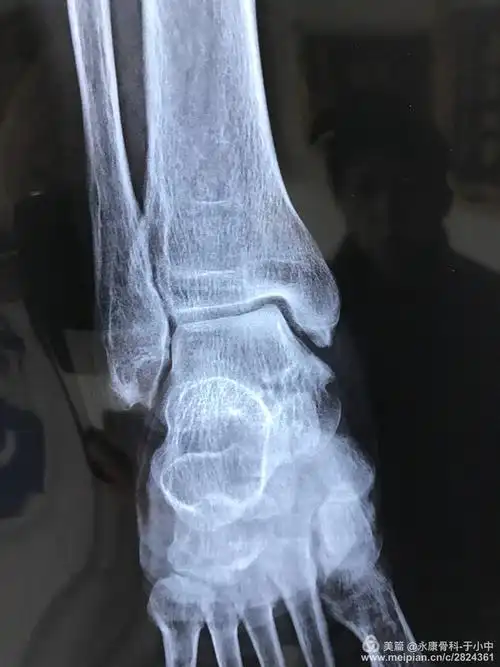

打篮球时脚崴了,右脚内侧骨头凸出来了,.该怎么办

脚前几天崴了不疼不肿,今天发现骨头有点突出没事吧